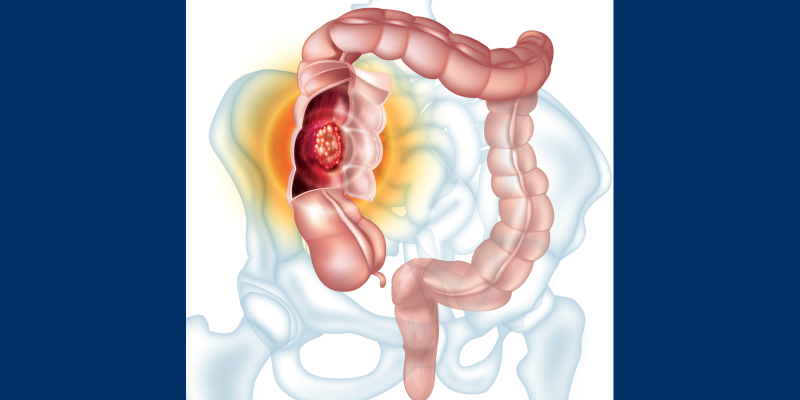

Surgical delays due to SARS-CoV-2 (COVID-19) are linked with shorter survival times in colorectal cancer, according to a new study published in the Journal of Gastrointestinal Surgery.

The COVID-19 pandemic caused mass cancellations of “non-emergency” operations to free up hospital beds and preserve personal protective equipment (PPE) for front-line healthcare workers. However, for many cancer patients, timely surgery is critical for survival. To evaluate the impact of delaying surgery for individuals with gastrointestinal cancers, researchers assessed the results of how surgical delays affect patients with colorectal, gastric or pancreatic cancer. They identified 43 relevant studies pertaining to colorectal cancer.

Following analysis, the results showed that a surgical delay of 30 to 40 days was correlated with shorter survival times in patients with colon cancer, as was a delay of seven to eight weeks after chemotherapy and/or radiation therapy in patients with rectal cancer. For pancreatic cancer, the investigators identified nine studies, and observed in two studies that cancer progression increased in patients who experienced surgical delays over 30 days. Moreover, six studies were included for gastric cancer, and none of the studies found worse patient survival outcomes with surgery delays.